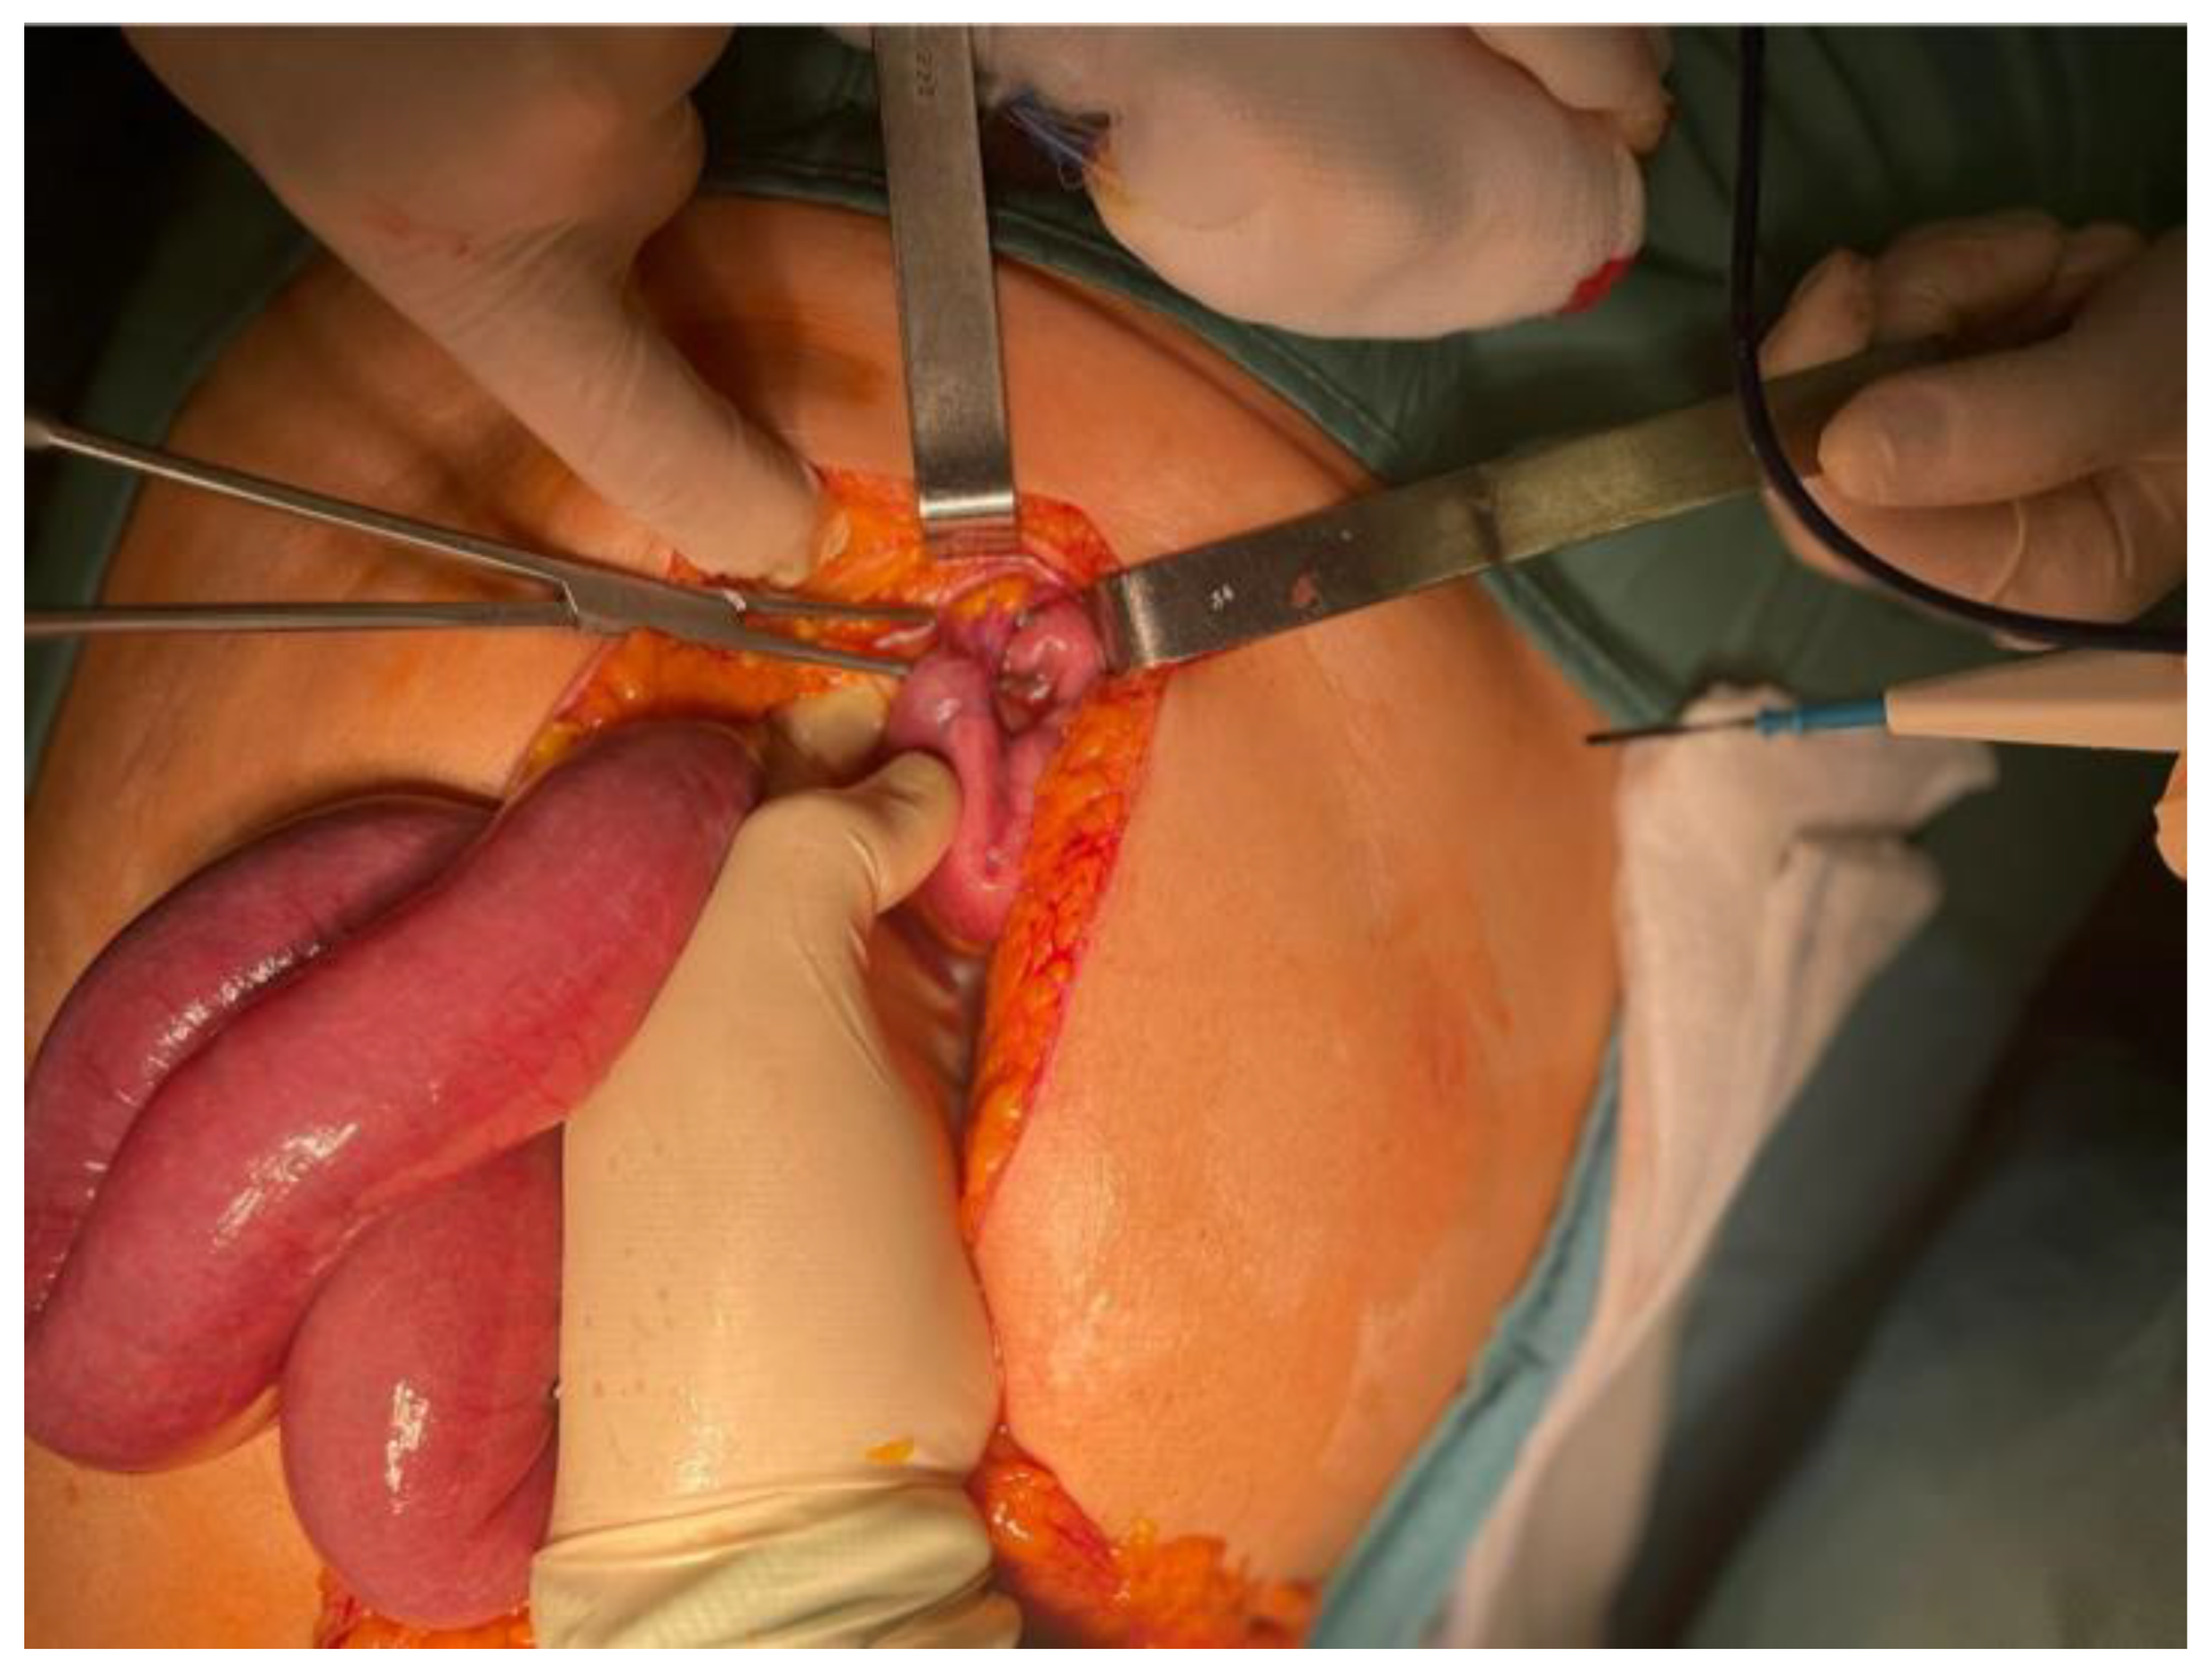

Given the imaging findings and the risk of strangulation, the patient was taken urgently to the operating room for exploratory laparotomy. Through a supra- and infraumbilical incision, the surgical team identified a segment of small bowel that had volvulated around a double fibrous adhesion band, resulting in venous congestion of the entrapped loops (Figure 6). The adhesions were carefully lysed, the volvulus was reduced, and the congested bowel was wrapped in warm saline-soaked gauze for fifteen minutes. During this time, the loop progressively regained normal color, peristaltic activity, and mesenteric pulsatility, confirming its full viability and eliminating the need for resection. A small segment of friable omentum was excised, a 24 French pelvic drain was placed, meticulous hemostasis was secured, and the abdominal wall was closed in layers.

Figure 6. Intraoperative photograph during exploratory laparotomy showing a volvulated ileal loop entrapped by a double adhesion band. After detorsion and warm packing, the bowel appears viable, allowing adhesiolysis without the need for resection.